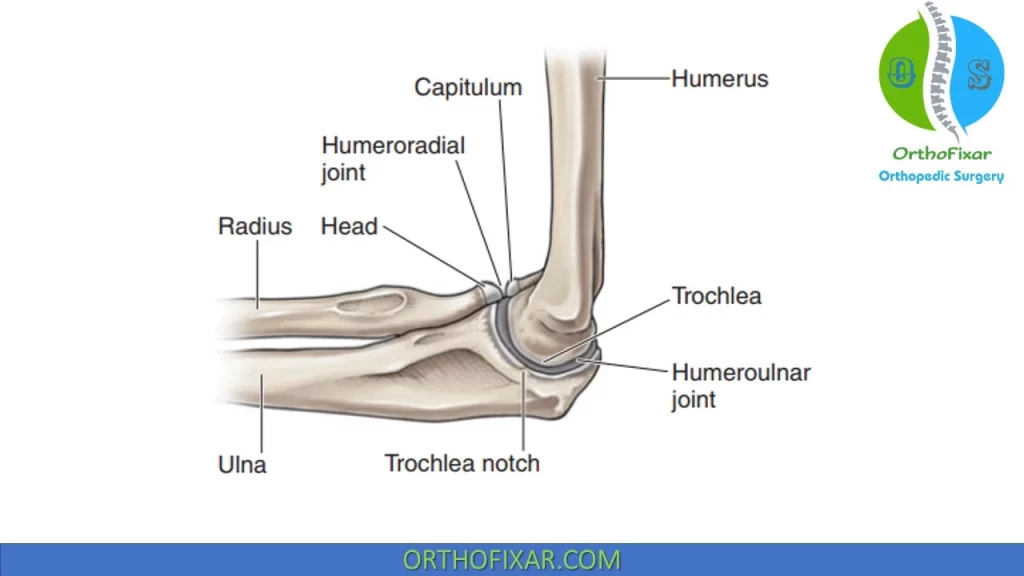

Elbow Arm Anatomy

Elbow Anatomy Full Easy Review OrthoFixar 2025

Elbow Joint Anatomy Movement Muscle involvement

The Elbow Joint Anatomy and 3D Illustrations